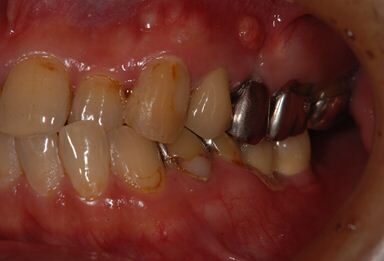

| 性別/年齢 | 男性 / 53歳 | ||||||||||||||||||||||||||||||||

| 主訴 | 左下奥歯2本のインプラント治療を希望。 | ||||||||||||||||||||||||||||||||

| 治療方針 | 左下欠損部分をインプラント治療にて機能的・審美的回復を行う。 | ||||||||||||||||||||||||||||||||

| 治療内容 | インプラント2本、ハイブリッドセラミッククラウン2本 | ||||||||||||||||||||||||||||||||

| 総治療費 | 399,000円 | ||||||||||||||||||||||||||||||||

| 治療期間 | 9ヶ月 |